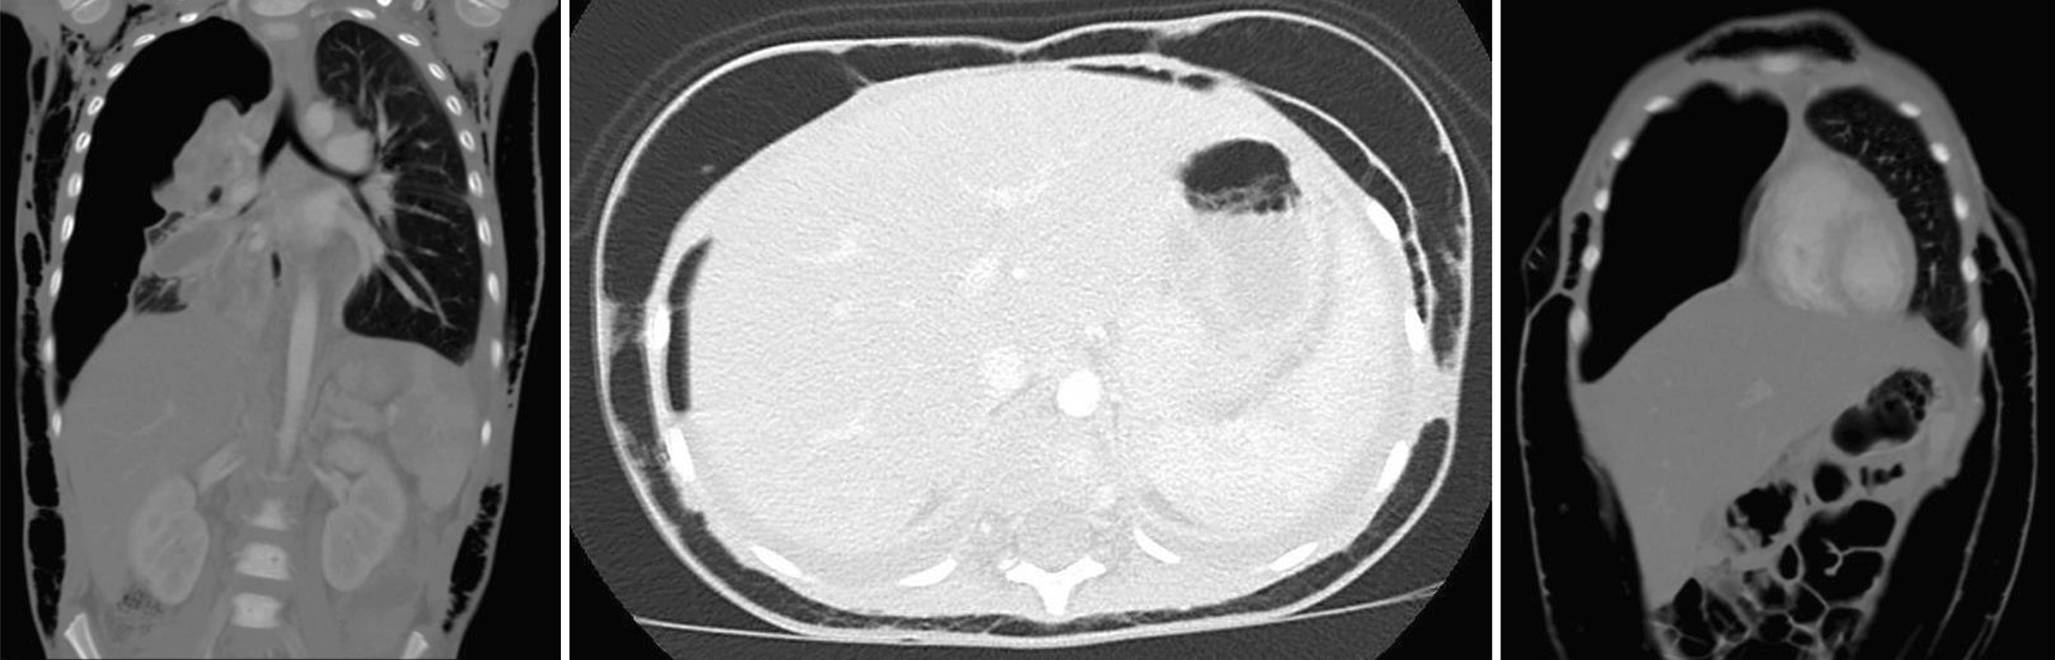

Ein dreijähriger Junge ist an einer komplizierten Pneumonie mit beidseitigem Pleuraerguss erkrankt. Die Anlage von Pleuradrainagen ist erforderlich. Nach sieben Tagen werden die Drainagen bei einem gebesserten sonografischen Untersuchungsbefund entfernt. Plötzlich quillt die Haut des Patienten auf. Die Pleuradrainage rechts wird daraufhin replatziert. Das Skrotum des Jungen bleibt während der folgenden Tage fast zum Platzen angeschwollen (Abb. 1 und 2).

Computertomografie des Thorax und des Abdomens (a–c). (© GKM)